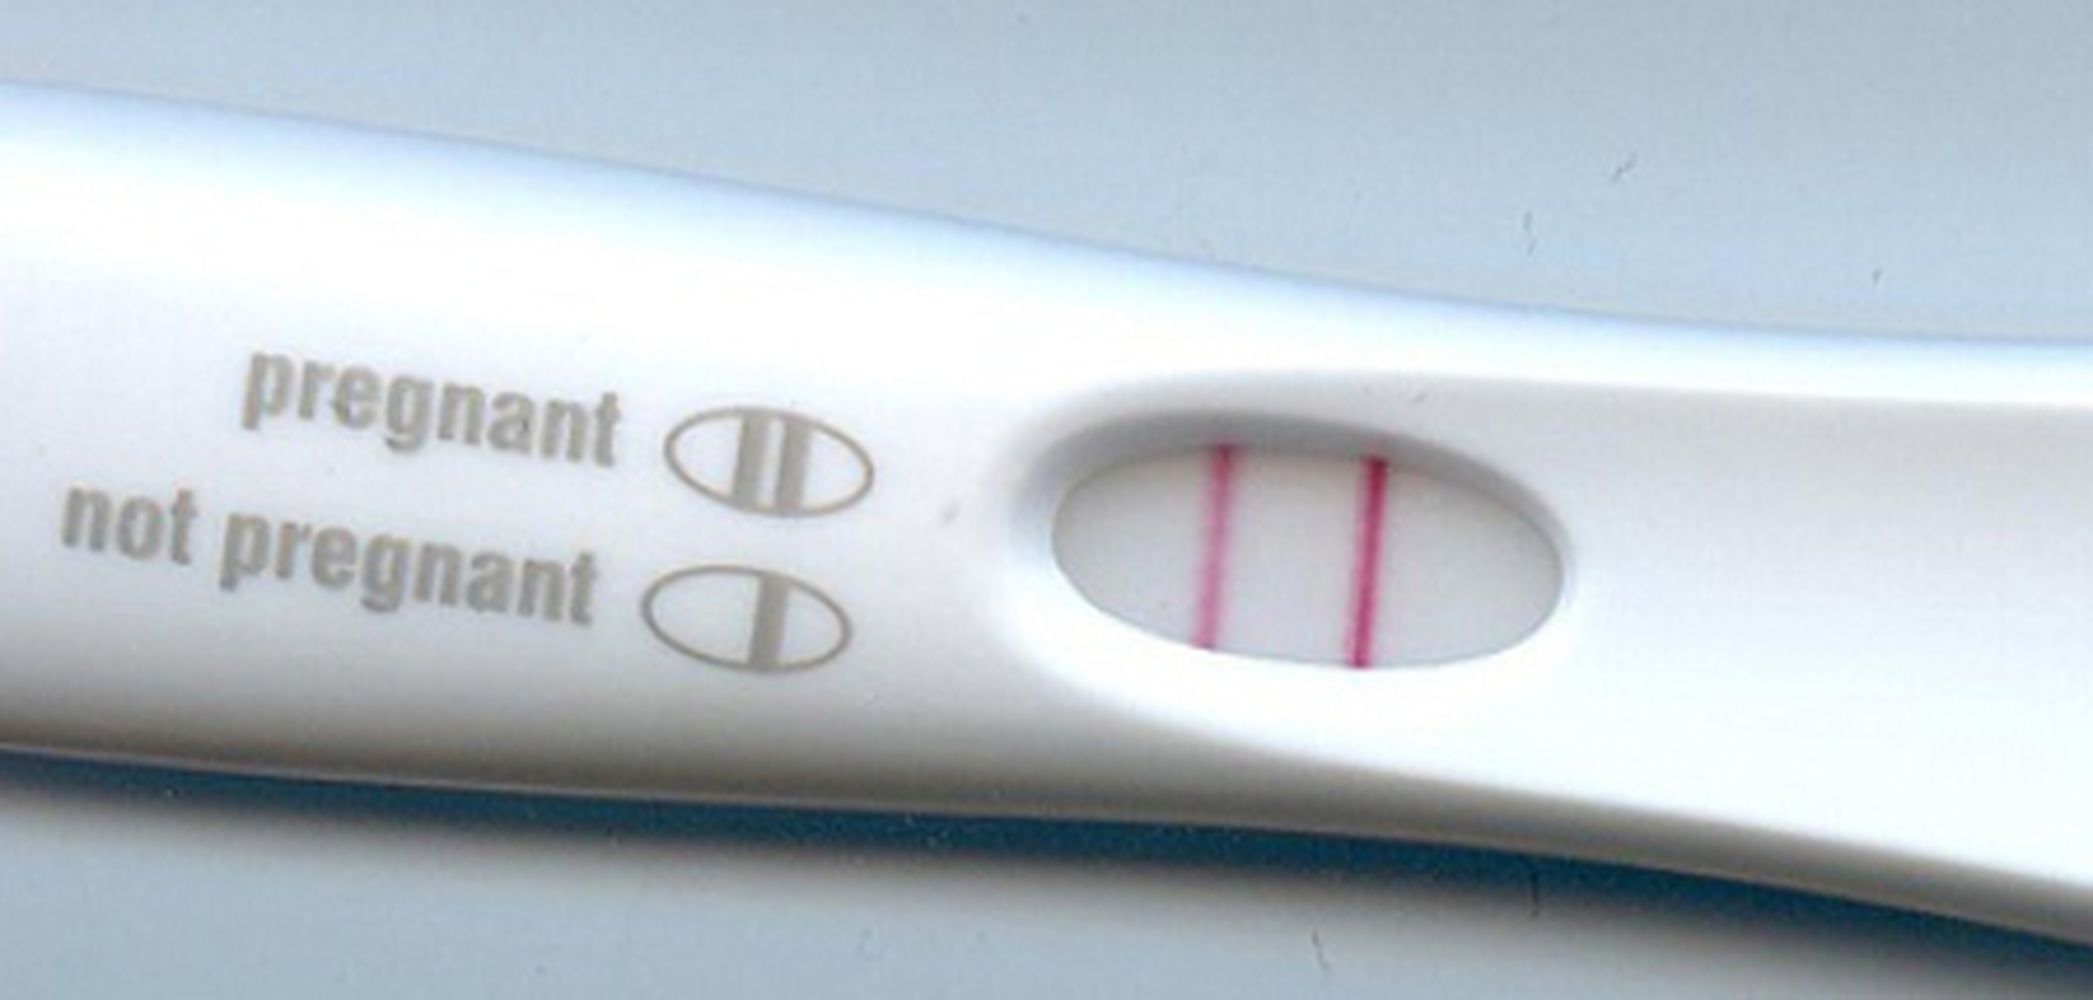

If the woman is pregnant, two coloured patterns appear. If she is not pregnant, only one appears.

A positive pregnancy test (Klaus Hoffmeier, public domain)